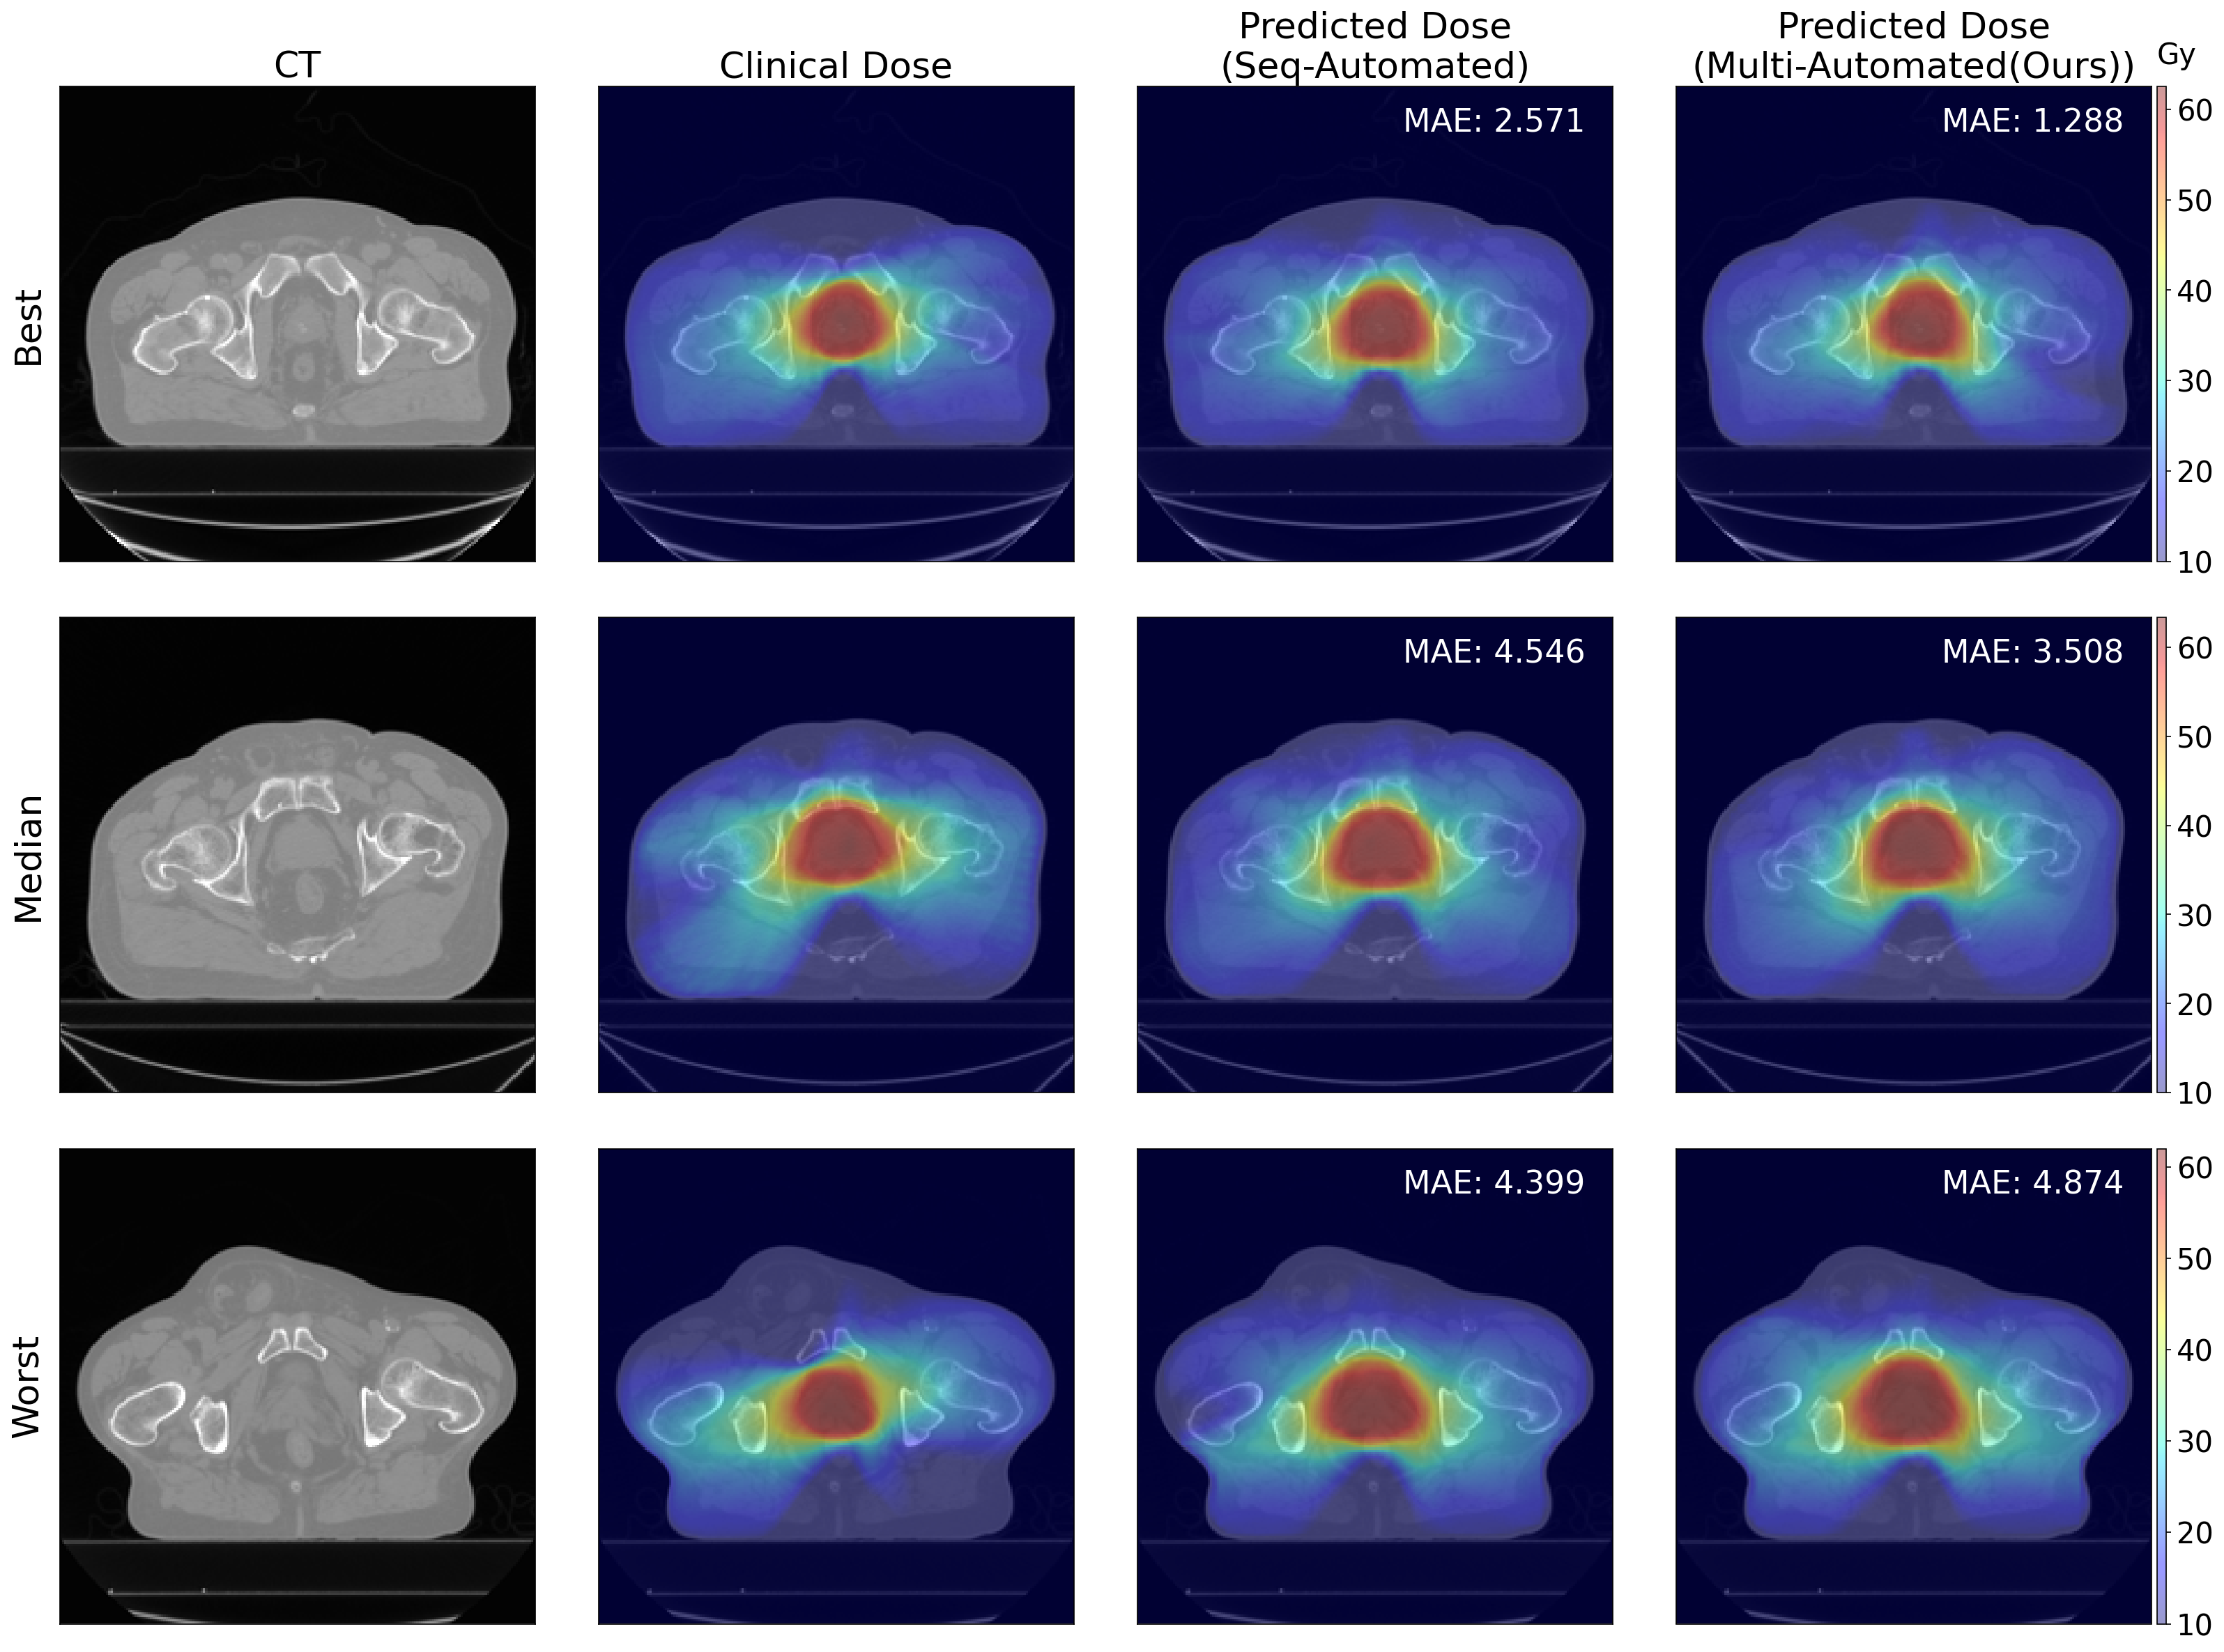

Furthermore, we computed relative difference in MAE to compare the performance of the baseline model with the two sequential models, Seq-Human and Seq-Automated. For the prostate dataset, Seq-Human outperformed the baseline model by 6.641% while Seq-Automated performed 10.28% worse than the baseline. This result demonstrates the quality of the DL ROIs are worsening the dose prediction performance when they are imperfectly contoured. For the OpenKBP dataset, however, baseline models outperformed both sequential models, Seq-Human and Seq-Automated, by 20.252% and 23.463%, respectively, note that the OpenKBP dataset is not originally designed for training contouring models, meaning that the provided contour information might not be perfectly curated. Meanwhile the relative difference of Multi-Automated is 7.132% worse than the baseline, which is still outperforming both sequential models with the large margin. However, Multi-Automated outperformed D0.1ccsubscript𝐷0.1𝑐𝑐D_{0.1cc}italic_D start_POSTSUBSCRIPT 0.1 italic_c italic_c end_POSTSUBSCRIPT and Dmeansubscript𝐷𝑚𝑒𝑎𝑛D_{mean}italic_D start_POSTSUBSCRIPT italic_m italic_e italic_a italic_n end_POSTSUBSCRIPT for right and left parotid, meaning that Multi-Automated better predicts the dose distribution for OARs. In Figure 2 and Figure 4, we visualized the dose prediction results using the prostate dataset, and OpenKBP dataset, respectively.

To validate the impact of multi-task learning for developing dose prediction models in automated radiotherapy, we compared the DVH-MAE scores of Seq-Automated with Multi-Automated which are both used without any human interventions. The average DVH-MAE of Seq-Automated and Multi-Automated were 4.301 Gy and 3.528 Gy for Prostate dataset, respectively. Especially the improvement of using Multi-Automated were significant (p <<< 0.05) in critical anatomical structures; Bladder (D30subscript𝐷30D_{30}italic_D start_POSTSUBSCRIPT 30 end_POSTSUBSCRIPT and D50subscript𝐷50D_{50}italic_D start_POSTSUBSCRIPT 50 end_POSTSUBSCRIPT) and in Right femur (D5subscript𝐷5D_{5}italic_D start_POSTSUBSCRIPT 5 end_POSTSUBSCRIPT, V22subscript𝑉22V_{22}italic_V start_POSTSUBSCRIPT 22 end_POSTSUBSCRIPT, and Dmeansubscript𝐷𝑚𝑒𝑎𝑛D_{mean}italic_D start_POSTSUBSCRIPT italic_m italic_e italic_a italic_n end_POSTSUBSCRIPT). For OpenKBP dataset, DVH-MAE of Seq-Automated and Multi-Automated were 11.650 Gy and 10.109 Gy, respectively, where Dmeansubscript𝐷𝑚𝑒𝑎𝑛D_{mean}italic_D start_POSTSUBSCRIPT italic_m italic_e italic_a italic_n end_POSTSUBSCRIPT of right parotid glands were significantly improved for Multi-Automated (p <<< 0.05).

Figure 2: This figure illustrates qualitative results of Prostate dataset, showing input CT scans, ground truth clinical dose distributions (Clinical Dose), and the dose distributions generated by sequential automated contouring and planning model (Seq-Automated) and the automated contouring and planning model using multi-task learning (Multi-Automated). The voxel-wise Mean Absolute Error (MAE) for both model outputs are provided. The figure presents best, median, and worst cases in terms of MAE from the test dataset